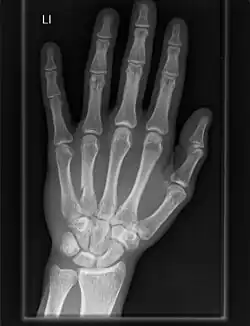

Clinical significance

Osteoarthritis of the carpometacarpal joints is a type of joint disease that results from breakdown of joint cartilage and underlying bone.[13] When it affects the thumb it is termed trapeziometacarpal osteoarthritis.

Carpometacarpal bossing is the presence of a small immovable protuberance over the joint.[14]